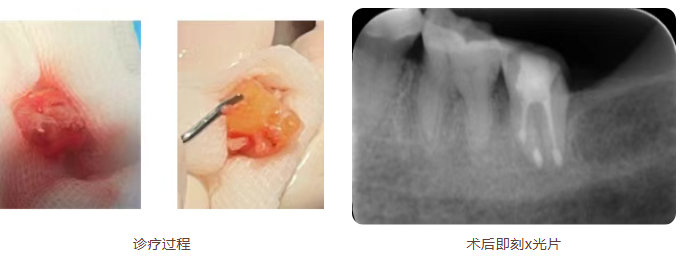

这是一种极具挑战性的技术,其核心是将牙齿完整拔除,在体外显微镜下进行精准的根尖切除、侧穿修补等操作后,再将牙齿植回原牙槽窝。

手术过程中,在护理团队的协助下,蒋医生在显微镜下逐步完成了所有精细步骤。最终,这颗经过体外处理的牙齿被成功植回。